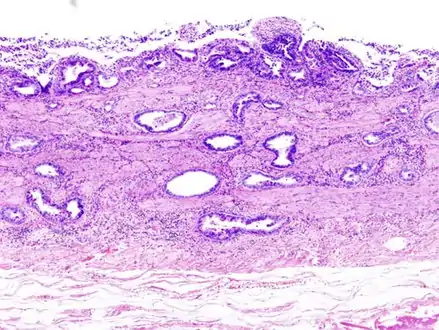

Gallbladder adenocarcinoma lymphatic invasion histopathology

Incidentally discovered gallbladder cancer (adenocarcinoma) following a cholecystectomy.

Gallbladder adenocarcinoma histopathology